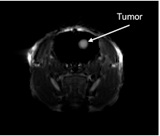

Nanoparticules excitables par des rayons X pour la thérapie photodynamique de glioblastomes multiformes

Une approche innovante du traitement des glioblastomes multiformes en combinant radiothérapie et thérapie photodynamique via des nanoparticules scintillantes.

Nanoparticules pour le traitement photodynamique vasculaire des tumeurs cérébrales guidé par imagerie